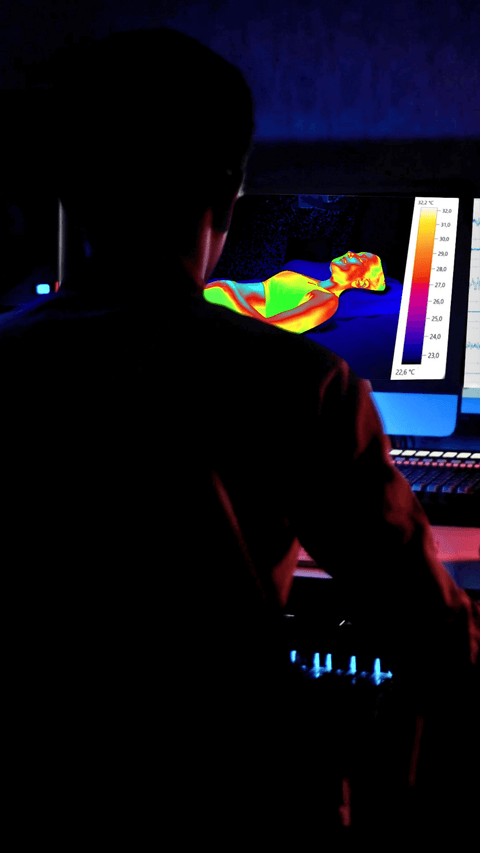

Analisi punti di pressione

Questa procedura misura come il peso del corpo viene distribuito sulla superficie di riposo. Durante l'analisi, un individuo si sdraia sul prodotto, e con l'ausilio di tecnologie avanzate si rilevano le zone dove il corpo esercita maggior pressione. Questo permette di identificare aree a rischio di stress o disagio, come le spalle, i fianchi o la zona lombare.